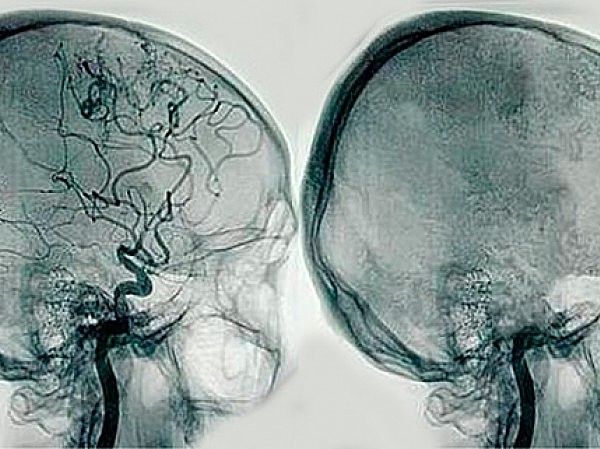

• Angiografía

Angiografía

Desarrollado por el neurólogo portugués António Egas Moniz.

Utiliza un catéter, la guía por rayos X y una inyección de material de contraste para examinar los vasos sanguíneos.